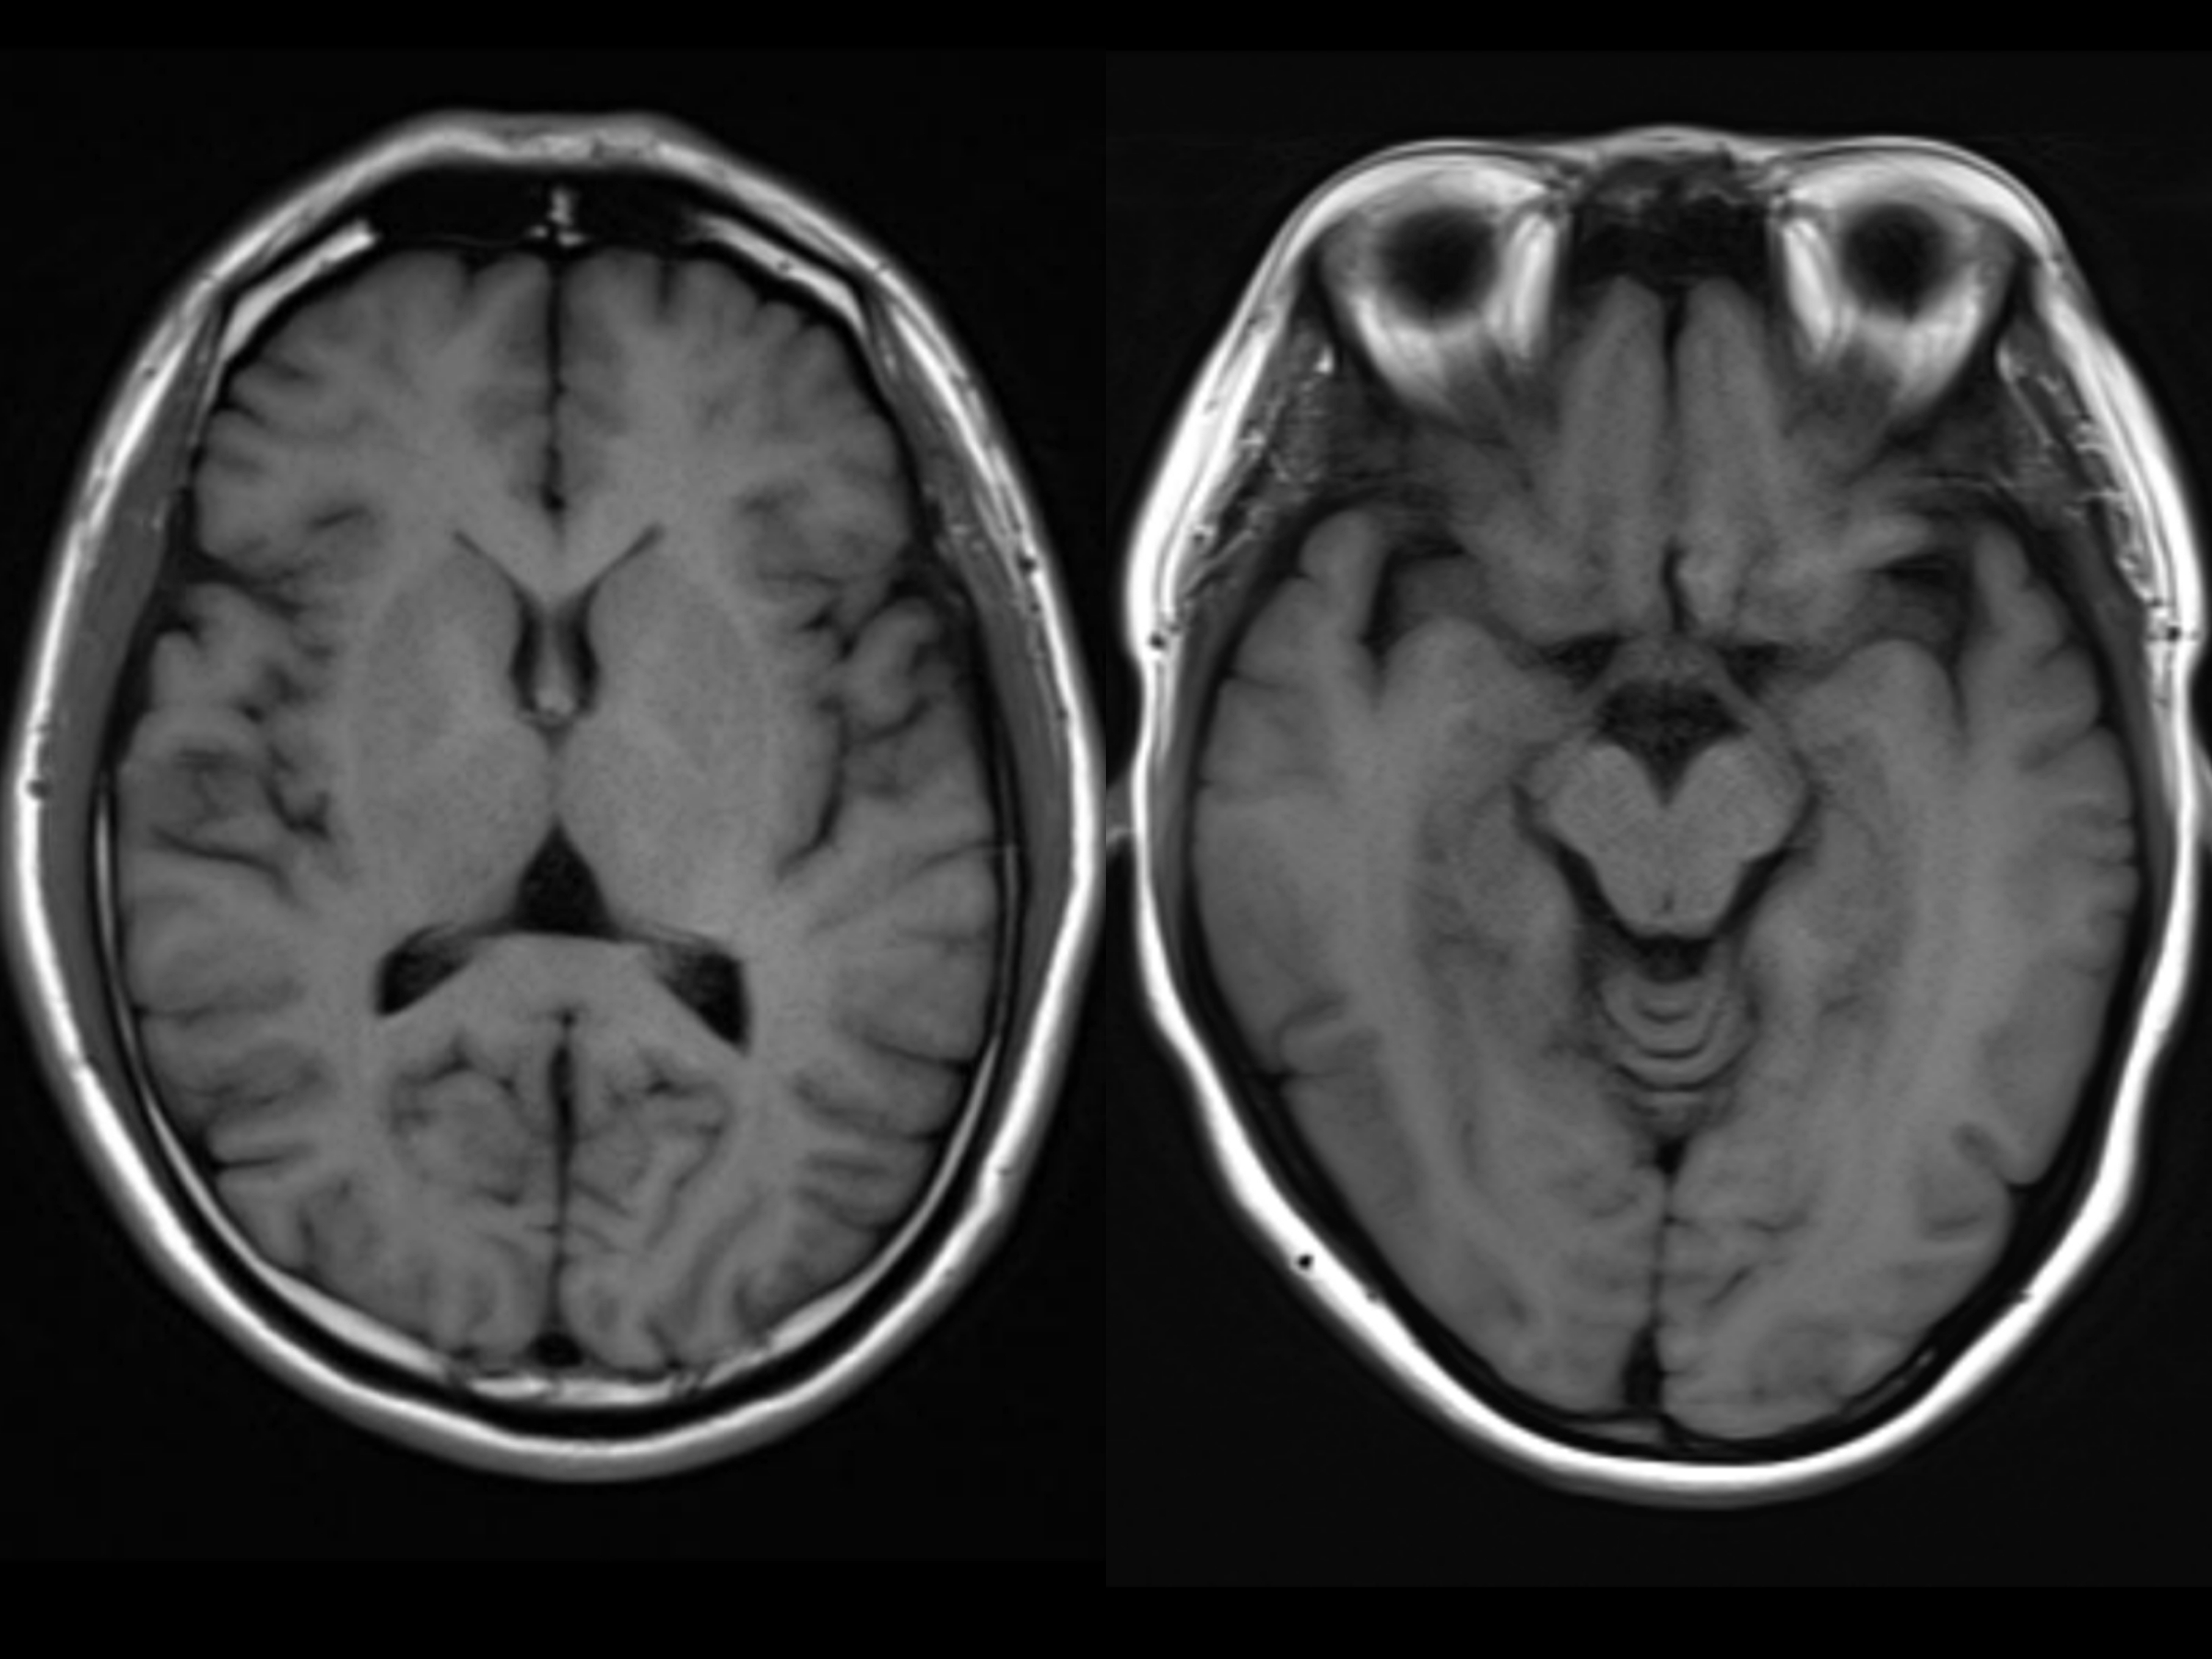

脑科讲坛:不能直接看到的衰老丨ct,核磁共振发现脑萎缩怎么办?

脑萎缩原本是在ct或mri检查时,发现脑组织体积减小和脑室扩大等而命名

脑科医生带您解读:ct/磁共振报告上的"脑萎缩"是不是病